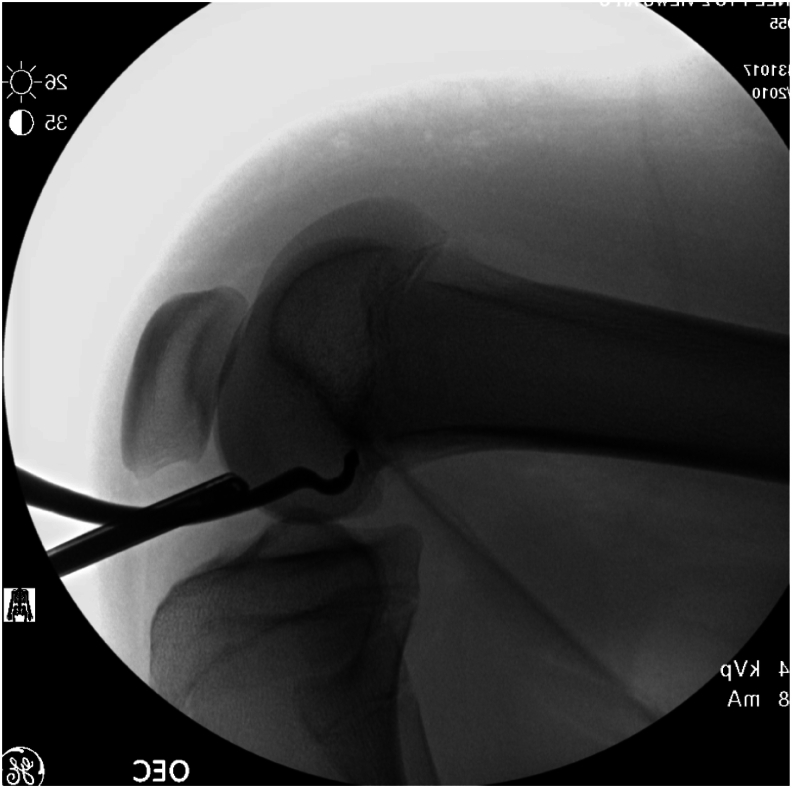

Lateral extra-articular tenodesis (LET), as an adjunct to anterior cruciate ligament (ACL) reconstruction, is gaining popularity among pediatric and sports medicine orthopaedic surgeons for the treatment of ACL injury, especially in the female, hyperflexible, and high-risk athlete population. The addition of LET or anterolateral ligament (ALL) reconstruction is typically recommended at the time of index ACL reconstruction surgery and is performed after the ACL graft is tensioned. Rotational instability has been described in cases where the ACL graft was malpositioned too vertically, and in those cases, ACL revision is indicated. In our case, ACL reconstruction was performed in isolation in a hyperflexible, high-risk (volleyball) female athlete, and she had persistent complaints of rotational instability despite an intact and well-positioned ACL graft on magnetic resonance imaging (MRI) scan. She demonstrated excessive internal rotation of the tibia in relation to the femur and exhibited symptomatic anterolateral instability on clinical examination, with a negative pivot shift but pain on internal rotation stress. She underwent a second surgery consisting of isolated modified Lemaire LET after examination under anesthesia (EUA) demonstrated negative Lachman and pivot shift. Second-look arthroscopy demonstrated an intact quadriceps autograft ACL graft. She recovered uneventfully, and her rotational instability problem was resolved. She returned to sports 12 months after the surgery and has been pleased with her result.

Key concepts: (1)Lateral extra-articular tenodesis (LET) can be added to increased rotational stability in the setting of anterior cruciate ligament (ACL) reconstruction.(2)Although typically added during the index procedure, it can be successfully completed later if needed.(3)The ACL confers both anteroposterior and rotational stability to prevent excessive anterior translation and excessive internal rotation of the tibia with respect to the femur.(4)LET can augment the ACL graft in preventing rotational instability in the setting of an ACL-deficient knee.